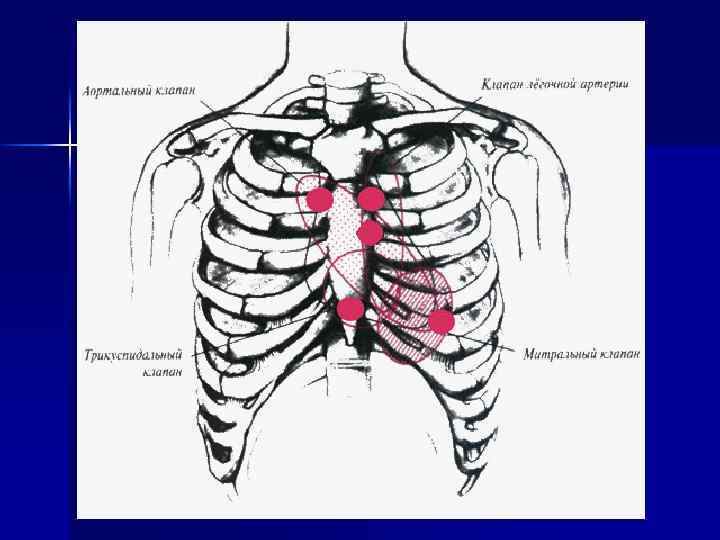

Точки выслушивания шумов Общие закономерности: 1) лучше всего шумы выслушиваются в точках аускультации тех клапанов, в области которых они образовались 2) шумы хорошо проводятся по направлению тока крови 3) шумы лучше выслушиваются в той области, где сердце прилежит к грудной клетке и не прикрыто легкими n

Особенности шумов при различных пороках сердца (1) Шум Систолический шум при недостаточнос ти митрального клапана Систолический шум при недостаточнос ти трехстворчато го клапана Систолический шум при стенозе устья аорты Место аускультации Область иррадиации Верхушка сердца 1) подмышечная область слева 2) II и III межреберье слева от грудины У основания Вверху и вправо, в области мечевидного правого предсердия отростка грудины II межреберье справа от грудины (грубый и громкий пилящий шум) 1) при аускультации над всей областью сердца 2) межлопаточное пространство 3) область сонных артерий

Особенности шумов при различных пороках сердца (2) Шум Место аускультации Область иррадиации Диастолический Ограниченный участок в шум при сужении области верхушки сердца левого АВ отверстия Диастолический Точка Боткина-Эрба шум при недостаточности аортального клапана Диастолический На ограниченном участке у шум при сужении основания мечевидного правого АВ отростка грудины отверстия Вдоль левого края грудины